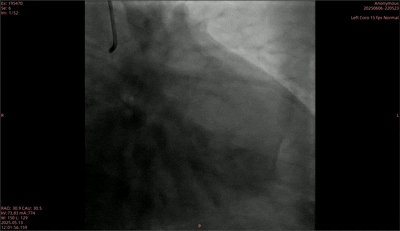

■ 术前评估

术前造影显示,前降支中段伴弥漫性长病变,狭窄最重80%,血流TIMI 3级;回旋支远段狭窄最重80%,血流TIMI 3级;右冠状动脉中段原支架血流通畅,支架内轻度内膜增生,血流TIMI 3级。经评估,治疗团队决定先治疗前降支病变且处理情况良好后,再采用矩正医疗冠脉血管重塑导管治疗患者回旋支远段。

术前